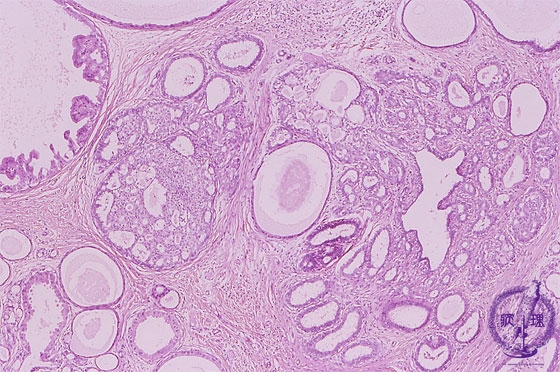

- 14.Breast

- (1)Mastopathy

Microscopic image(HE stain, low power view):Mastopathy is typically represented by a non-inflammatory/neoplastic lesion. Typically hormonal abnormalities are thought to be involved. Characterized by the concomitant proliferative and degenerative changes such as cyst formation, ductal hyperplasia, and sclerosing adenosis.